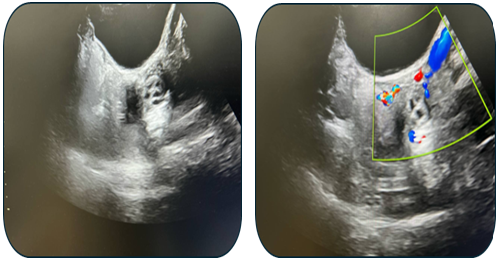

Case 2: An 11-year-old female presented with a torsed, edematous left ovary (69x49 mm) on ultrasound (Fig. 6). Laparoscopic detorsion alone was performed (Fig. 7 & Fig. 8). Serial postoperative ultrasounds documented the gradual resolution of edema and the return of vascularity by day 20 (Fig. 9), confirming ovarian recovery. | Figure 6. Preoperative ultrasound examination of the left ovary |

| Figure 9. Ultrasound examination on postoperative day 20 |